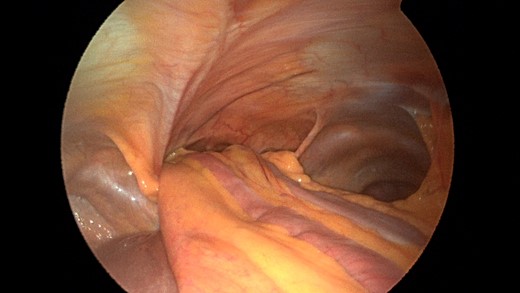

Patient underwent a laparoscopic approach in lithotomy positioning with the primary surgeon working between the legs. Three working ports were used, a 12 mm port at the umbilicus and two 5 mm ports; one in the LUQ and one in the RUQ. Upon initial laparoscopy multiple loops of small bowel were progressively reduced out of the hernia sac which also included the ascending colon and part of the transverse colon (Figs 3 and 4). All the small bowel and the colon appeared viable. The redundant parietal peritoneal hernia sac was excised out of the right inferior hemithorax utilizing a LigaSure (Covidien) (Fig. 5). The falciform ligament was also taken down all the way to the diaphragm. The defect in the diaphragm measured to be approximately 9 cm by 4 cm. A section of Pariatex composite mesh was then trimmed to 2 cm in width by 9 cm in length. Three stay sutures of 0 Ethibond were placed laterally and in the middle of the mesh. This was placed into the peritoneal cavity after soaking it in vancomycin with local anesthetic. The sutures were then percutaneously brought through the diaphragm edge that was unattached to the anterior abdominal wall and then subsequently through the anterior abdominal wall. These were then tied thereby re-approximating the unattached edge of the diaphragm to the anterior abdominal wall near the xiphoid (Fig. 6). Additional 0 Ethibond sutures were placed in between these initial ones percutaneously with a suture passer.

Laparoscopic view of the retroxyphoid defect in the diaphragm demonstrating multiple loops of small bowel and colon.